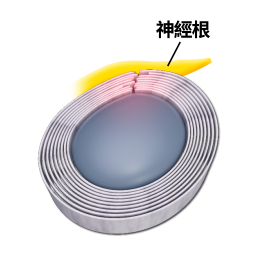

「頸源性頭暈」便是指疾病是與頸部問題最為相關。頸是連接頭部與軀幹的橋樑,它包含脊椎、血管 和神經組織(Fig.1),對活動和生存至關重要,任何傷害這條橋樑或這條橋樑出現病患,對維持人體健康或身體機能有關鍵影響,例如: 出現長期的頭暈頭痛。

主要頸源性頭暈、頭痛的成因: (1)上頸椎神經受壓:

因為頸椎分為上頸椎和下頸椎,頸椎C3節為分介線,C3以上椎節為上頸椎節,C3以下椎節為下頸椎節。凡是上頸椎神經受壓,例如:椎間盤突出、椎孔狹窄、椎體移位或下陷,都會有機會導致前額痛、後枕痛、眼窩痛、上頸椎痛。